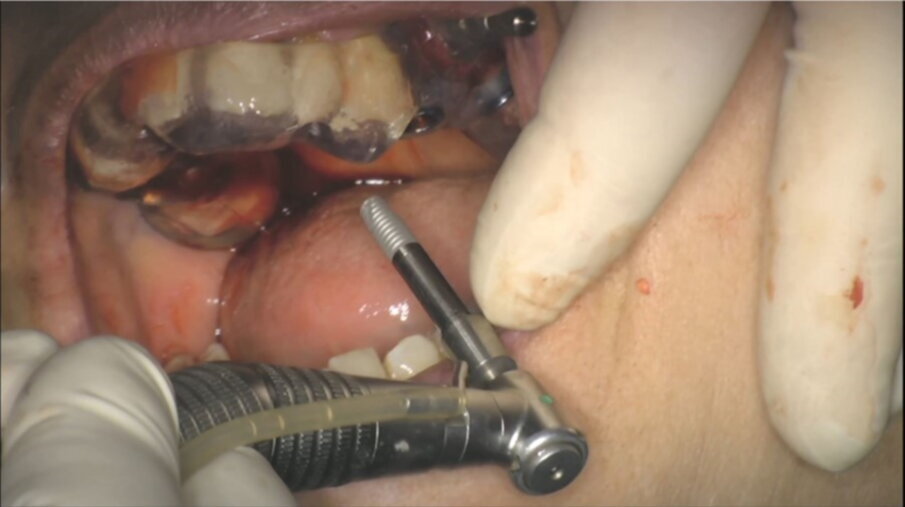

Fig. 47_Inserimento impianto.

Figg. 48, 49_Inserimento impianto.